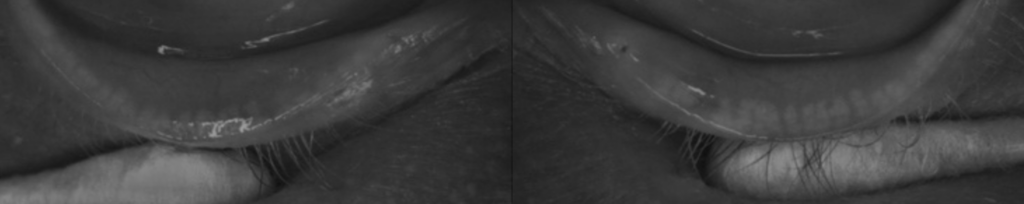

In our practice, we have also observed a number of cases of permanent structural changes in MG morphology in patients presenting with dry eye several years after discontinuing isotretinoin therapy. Meibography imaging in Figures 3 and 4 demonstrate the permanent structural changes commonly seen in these patients relative to the scale provided in Figure 2.